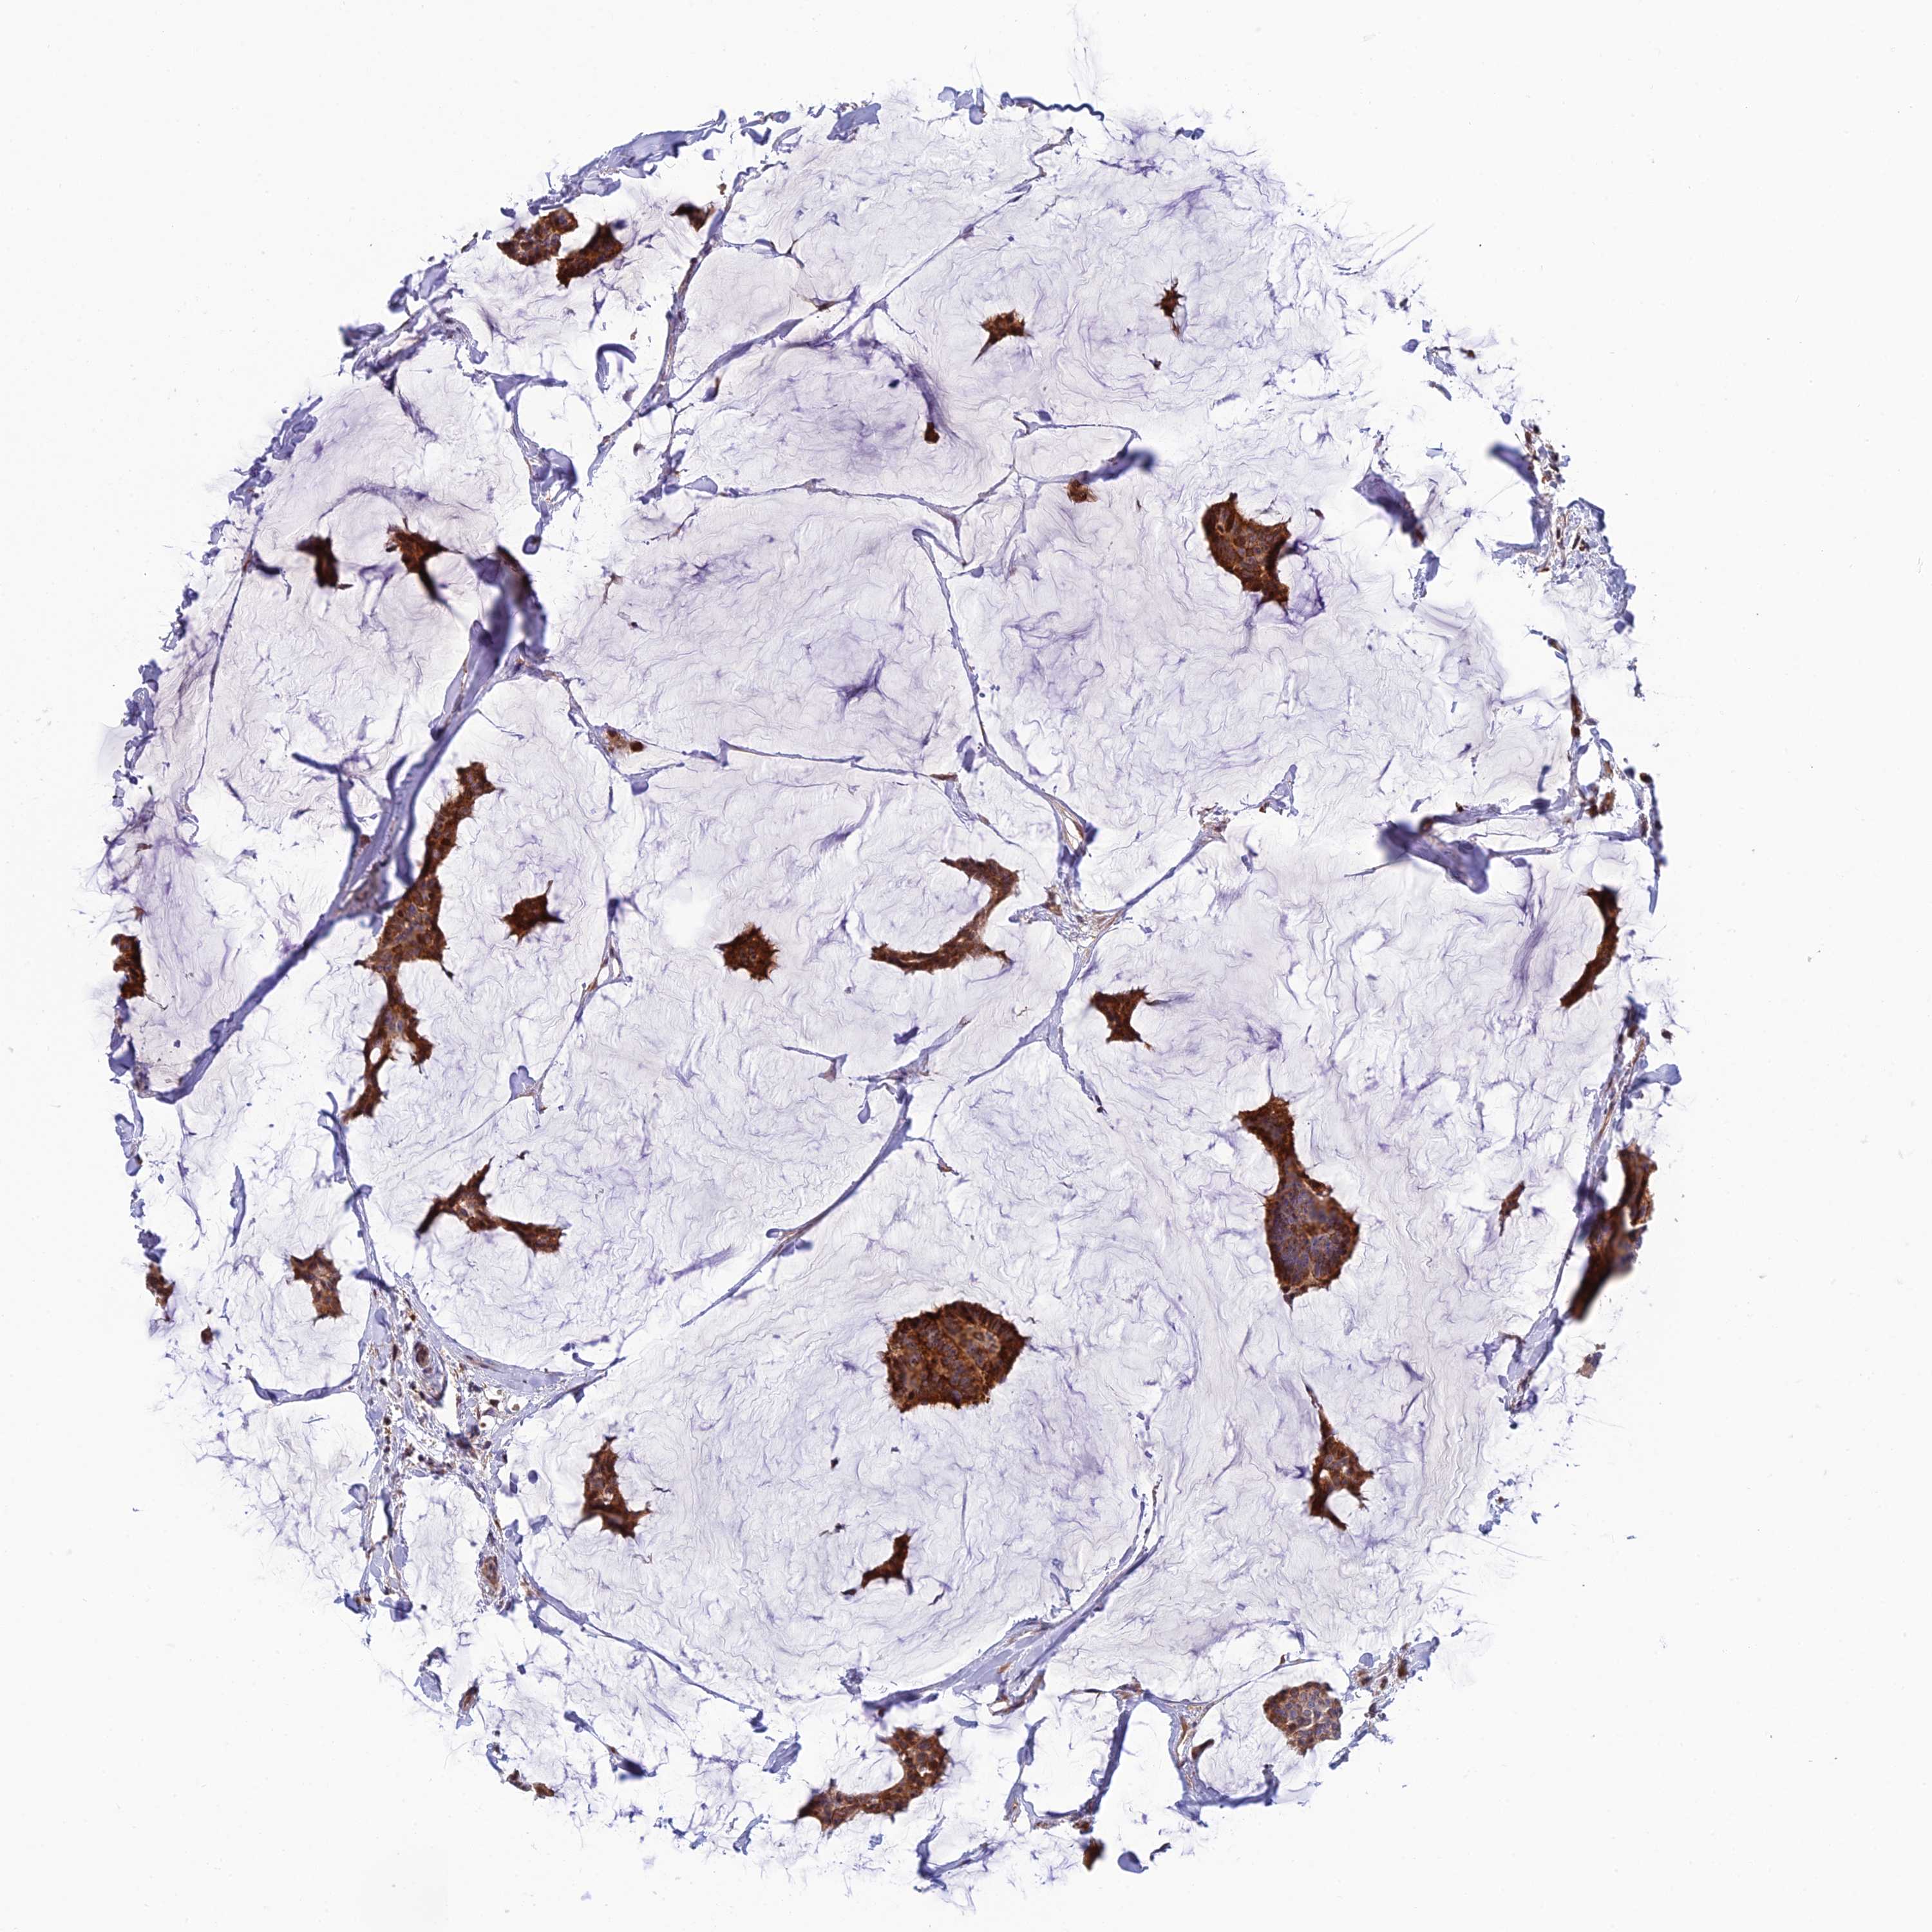

BRCA TCGA BRCA VALIDATION PROTEIN EXPRESSION

ANTIBODIES

AND

VALIDATION